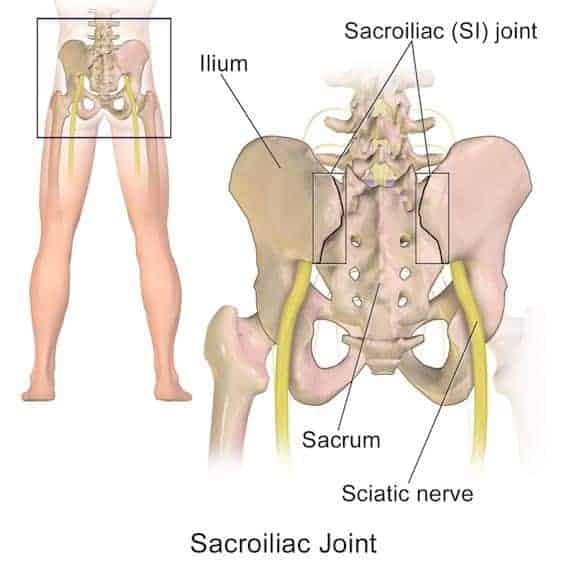

The sciatic nerve originates from the spine, running the length of the leg from buttocks to toes. It’s responsible for sensation and controlling the posterior aspect of the legs including the hamstrings, calves and bottom of the feet.

If the nerve is impinged at any point, it can cause discomfort, tingling, numbness or weakness anywhere down the back of the leg from glutes to toes.

Sciatica is typically the result of a pinched nerve in the lower back; the nerve may be compressed within or adjacent to the spinal canal as it enters the leg.

Several conditions that can cause sciatica:

- Piriformis Syndrome; this is when the Piriformis muscle, which is deep in the buttocks, becomes too tight or spasms – putting pressure on the sciatic nerve

- A herniated lumbar disc; this is the most common cause of sciatica, it happens when the herniated disc puts pressure on the sciatic nerve

- Spinal stenosis; essentially a narrowing of the intervertebral foramen (the hole the nerve comes out), which places pressure on the sciatic nerve

- Spondylolisthesis; An actual slippage of one vertebra that moves it out of line with the one adjacent to it